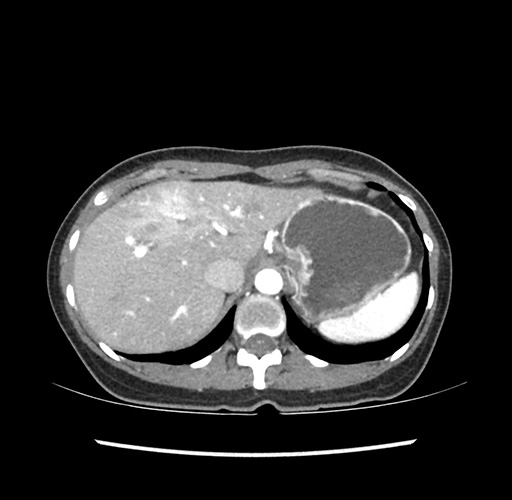

Imaging Analysis

Look through the patient's CT scan to identify any areas of concern for the necessary procedure.

Based on your CT findings, which issue(s) would give reason for "planned slowing down moment(s)" in this case?